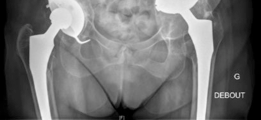

Anteroposterior (AP) pelvis:

Demonstrated significant superior and medial migration of the left acetabular component with evident periacetabular osteolysis. Lucency lines exceeding 2mm were observed at multiple interfaces, particularly zones 1 and 3 of DeLee and Charnley. There was evidence of prior bulk allograft incorporation, but with signs of partial resorption and failure to fully integrate into the host bone in areas of stress shielding. The femoral component appeared well-fixed in comparison.

This image likely represents the immediate post-operative radiograph, clearly demonstrating the Burch-Schneider cage in situ, the cemented polyethylene liner, and the well-positioned femoral stem, with initial bone graft material visible.